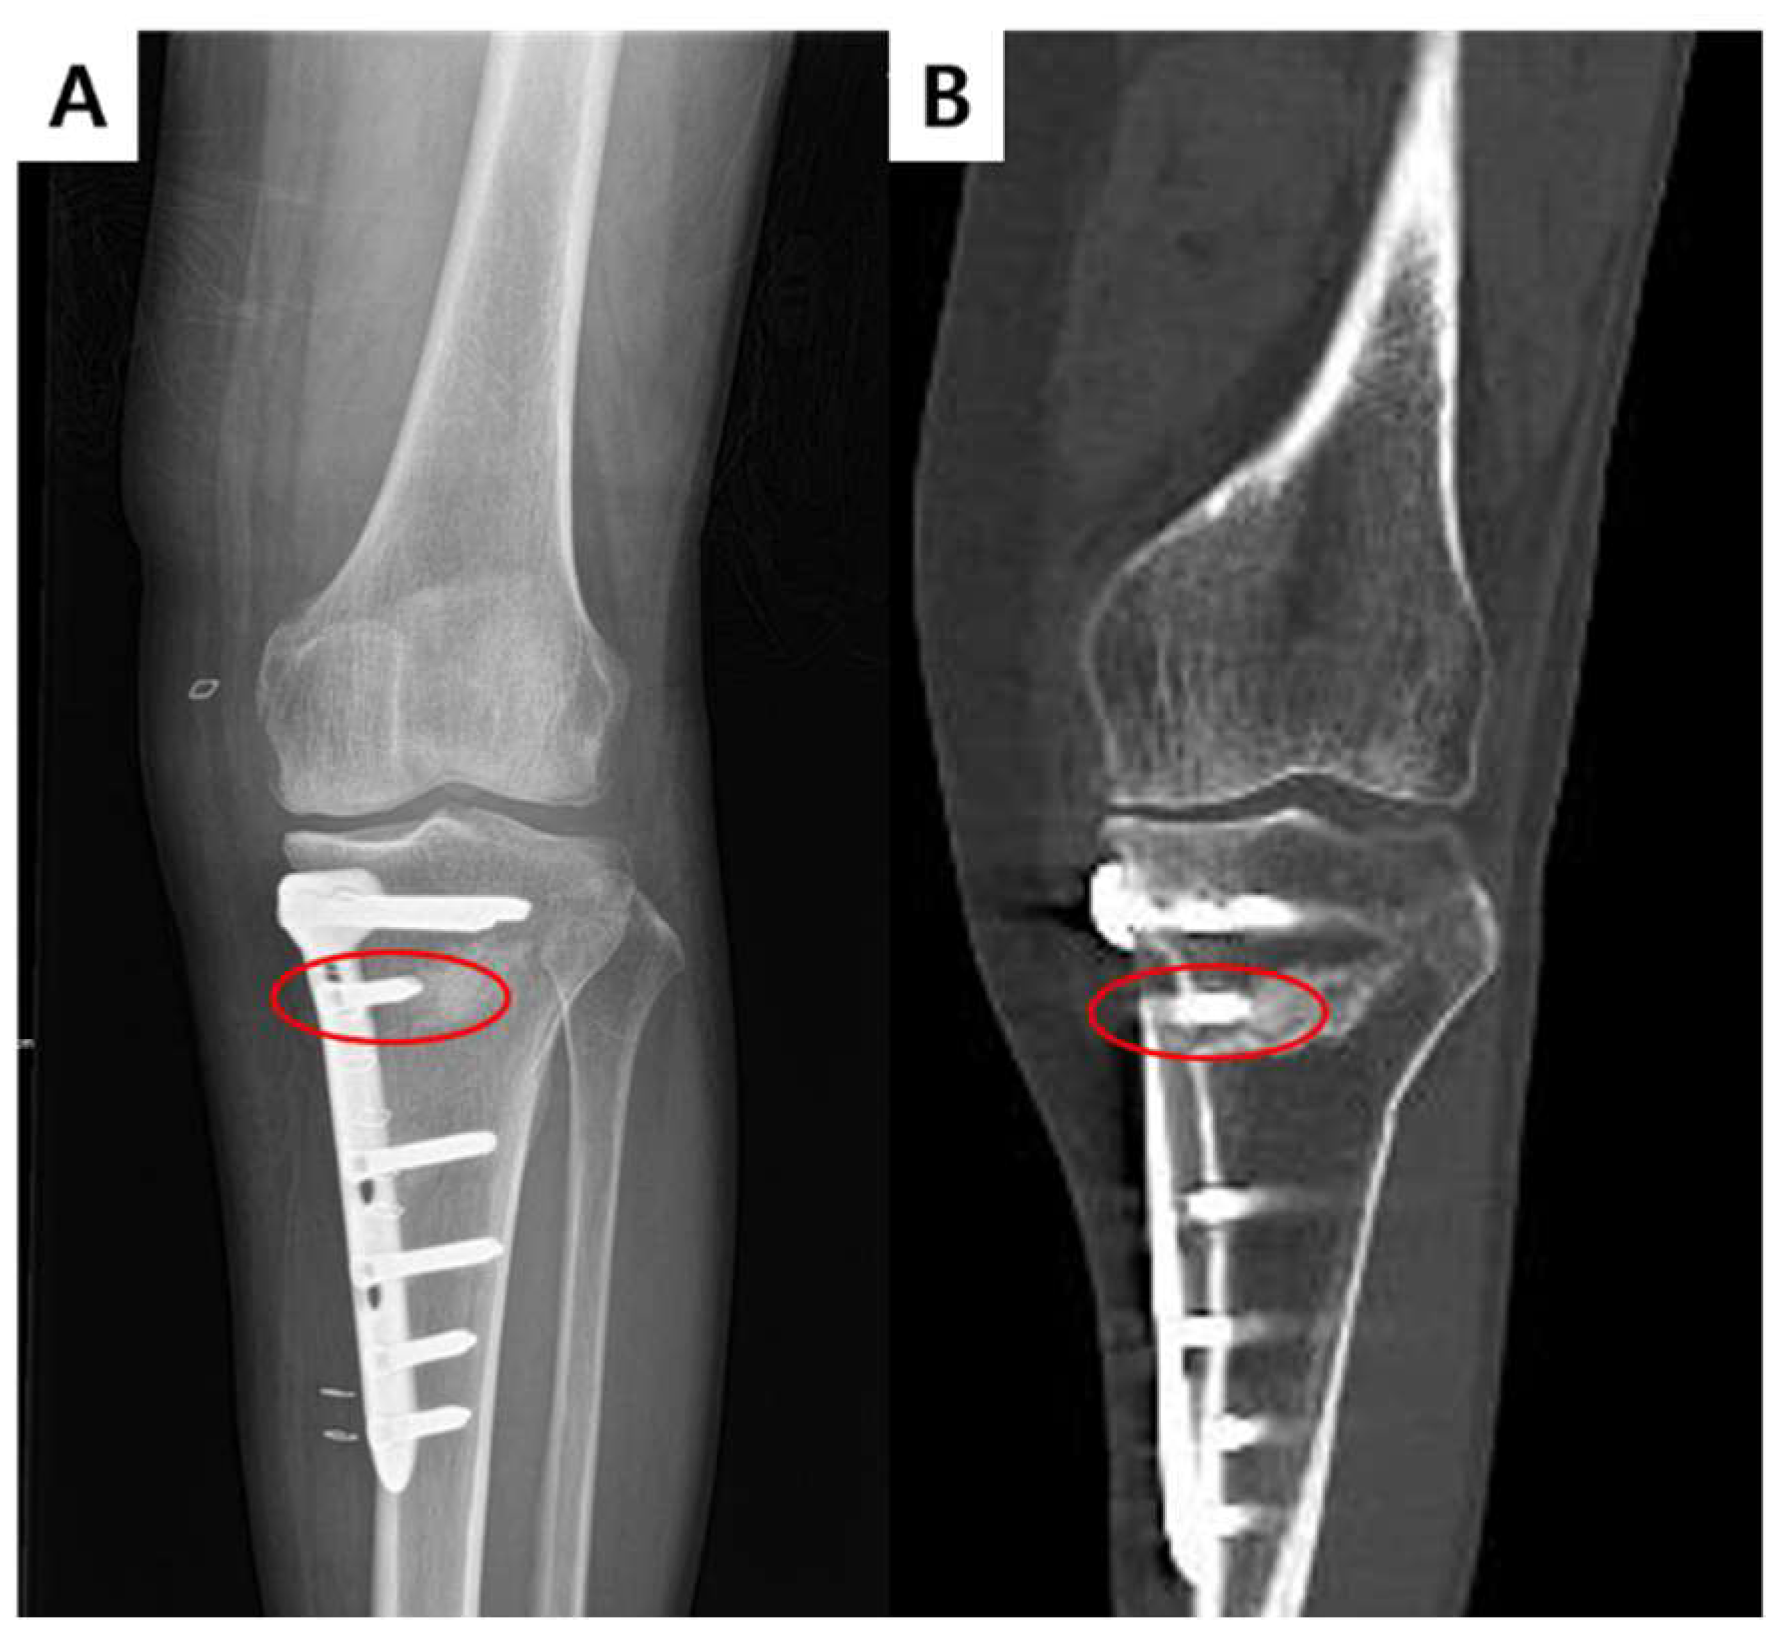

3.1. D-Hole Violation Simulation